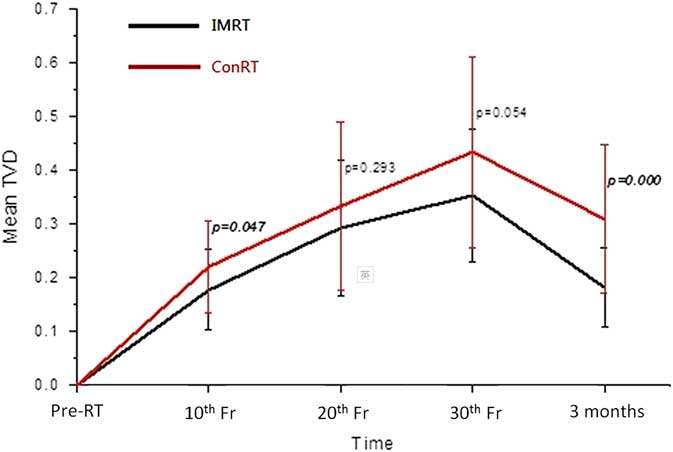

Displacement of parotid gland

The centroid of the parotid gland demonstrated movement during the treatment course, in which the displacement in x- (medio-lateral) direction was the greatest followed by the z- (supero-inferior) and y- (antero-posterior) directions (Table 3). At 30th fraction, the centroid had moved medially, superiorly and posteriorly from the original position. This pattern was demonstrated by both ConRT and IMRT groups, and there were no significant differences in displacement between the two groups. For both groups, the TVD of the centroid demonstrated an increasing deviation during the treatment course, and then moved back to some extent at 3 months after treatment (Figure 5). The ConRT group showed greater TVD than the IMRT group, but their differences did not reach statistical significance except at 3 months post-RT interval (p<0·001).

Figure 5 Comparison of the mean total vector displacement (TVD) of centroid of parotid glands between the conventional radiotherapy (ConRT) and intensity-modulated radiotherapy (IMRT) plans over the radiotherapy course up to 3 months after treatment. Note: The horizontal lines indicate the error bars.

With regard to the geometric changes of the parotid gland during radiotherapy, our study demonstrated that there were no significant differences between patients treated by ConRT and IMRT. For both groups of patients, the parotid gland demonstrated continuous shrinkage and medial migration during the treatment course. They were reflected by the increase of Δ%V, DSC and TVD from pre-treatment to 30th fraction, respectively. The shrinkage of parotid glands during radiotherapy has been reported in previous studiesReference Barker, Garden and Ang 16 , Reference Zhang, Lin and Wu 17 and it was mainly caused by the loss of gland parenchyma and acinar cell atrophy due to high dose radiation.Reference Radfar and Sirois 18 , Reference Wang, Yan and Zhang 19 The volume reduction of the parotid gland subsequently changed its shape and therefore resulted in a similar trend in DSC as for Δ%V. This medial migration of the parotid gland during radiotherapy was caused by the shrinkage of radiosensitive NP tumour, which was situated medially to the parotid gland and created space for the parotid gland to move in. Another associated factor could be due to the weight loss of the patients, whose head size became smaller leading to the lateral structures moved closer to the mid-plane. Actually such medial movement of the parotid gland during radiotherapy course has been reported by some studies.Reference Fung, Wu and Teo 20 , Reference Barker, Garden and Ang 21 Our study has shown that NPC patients generally had gradual weight loss during a course of radiotherapy. This was reflected by the reduction of the lateral head dimension. The phenomenon of weight lost, however, may vary across other institutions depending on nutritional support given. This is a common phenomenon for head and neck cancer patients as a result of poorer nutritional status due to radiation induced oral mucositis and xerostomia. The effect would be compounded with concurrent chemotherapy, which is commonly applied for stage II disease or above for NPC patients.

Due to the better target dose conformity in IMRT plans, they were more effective in sparing the parotid gland than the conRT plans in NPC patients. This was proven in our study in which the average mean parotid dose of the IMRT group was about 12 Gy lower than that of the ConRT group. This was also the reason that higher prescribed dose to the target could be given in IMRT than in ConRT plans, which subsequently led to better tumour control.Reference Au, Ngan and Ng 22 , Reference Yan, Cao and Wang 23 Although the geometric changes of the ConRT group appeared relatively greater than that of the IMRT group during the radiotherapy course, their differences did not reach significance. This implied that the extra dose delivered by the ConRT to the parotid gland did not lead to significant geometric change during the treatment course. The possible reasons were because the mean doses of both groups had already exceeded the recommended tolerance mean dose of 25 Gy,Reference Deasy, Moiseenko and Marks 24 the extra dose delivered by the ConRT would not cause significant increase of parotid gland damage. Nevertheless, the results obtained at 3 months after treatment demonstrated that IMRT plans showed better recovery of parotid gland volume, shape and centroid position. For instance, the mean parotid volume returned to 85% of pre-treatment volume in IMRT group, compared with 75% in ConRT group. This indicated that although the rate of parotid gland damage was similar during the course of radiotherapy, the rate of recovery after completion of treatment was different between the two techniques. It has been reported that parotid recovery took place after completion of radiotherapyReference Hey, Setz and Gerlach 25 which were in line with the geometric changes obtained in our study. In addition, study by Hey et al.Reference Hey, Setz and Gerlach 25 reported that the recovery process of the parotid gland could be dose dependent. It was also proposed in some studies that stem cells in the parotid gland were responsible for the post-RT repair if they were not eliminated in the treatment course.Reference Feng, van der Zwaag, Stokman, van Os and Coppes 26 As the more conformal IMRT plans are better equipped to limit the high dose to a smaller volume, and deliver lower mean dose to the gland, it can help to preserve more stem cells in the gland and facilitate better recovery. The improved recovery of the parotid gland in the IMRT cohort may be attributed to this improved opportunity for stem cell recovery.